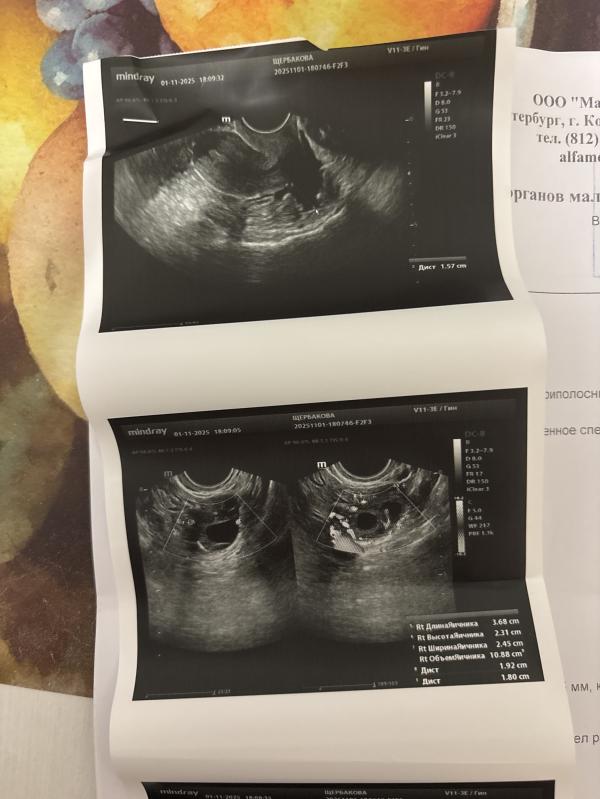

А так это узи на 21дц